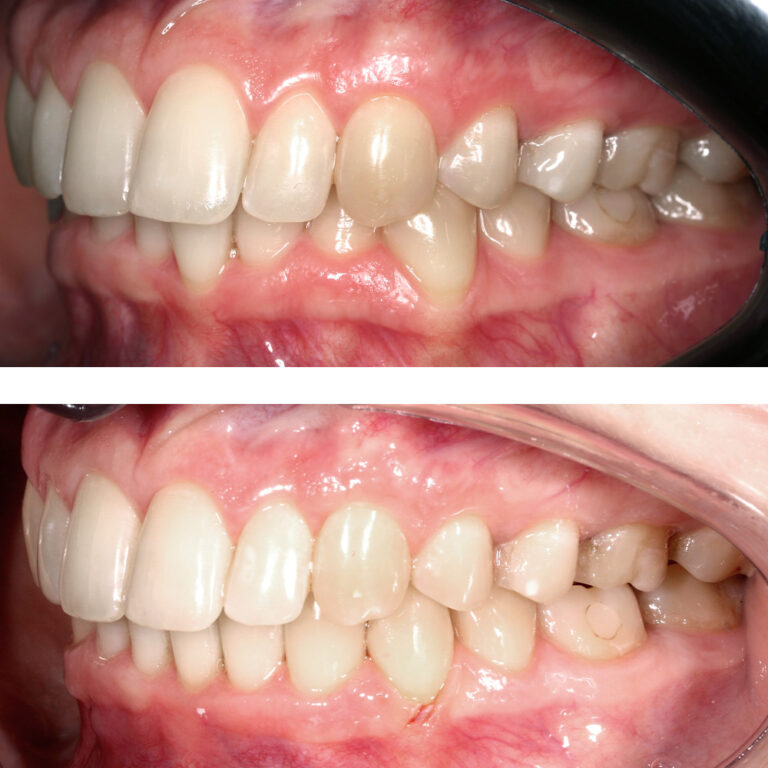

Кейс 13

Булгач (Мочалова) Галина Игоревна

Количество кап ВЧ 19

Количество кап НЧ 24

ДО

ПОСЛЕ